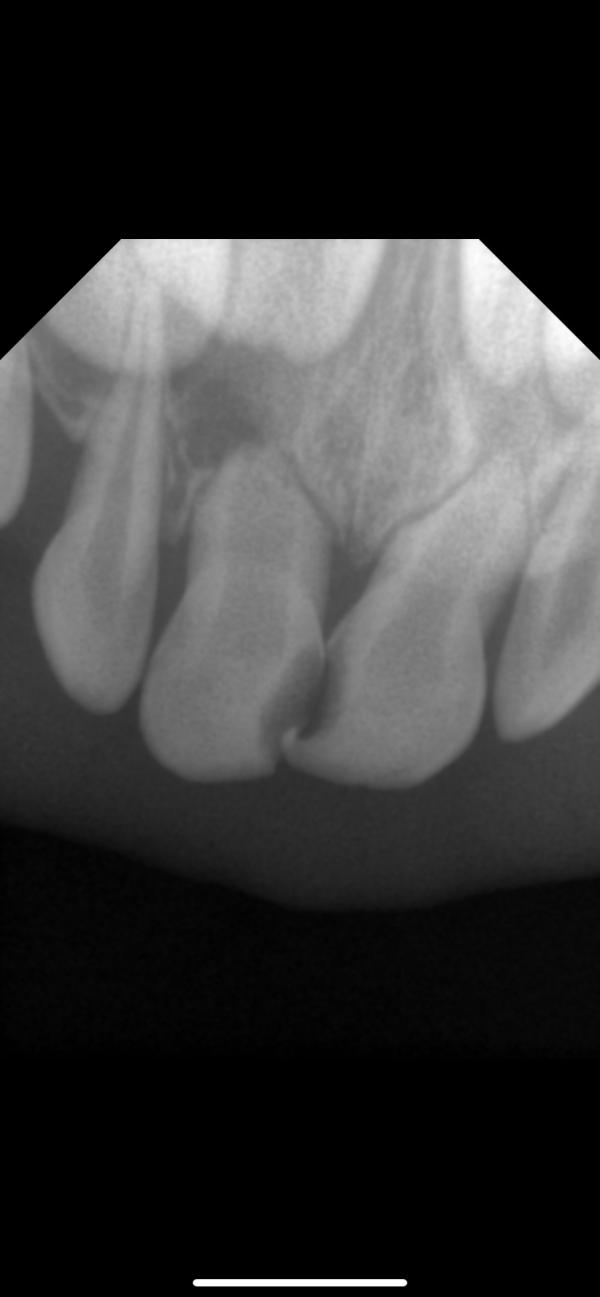

На фото есть гной?

Были у стоматолога,сказали удалять 3 зуба,в том числе передние,в другой стоматологии сказали,просто пульпит,вот думаем не раскручивают ли нас на деньги

@isdarja, да, где затемнение на корне. У обоих единичек корни рассасываются уже, смысла их лечить никакого по сути нет. Но тот, что с воспалением, может повредить зачаток постоянного

Левую единицу удалять 100%. Остальные хорошо бы переделать снимки в другой проекции, не совсем понятно